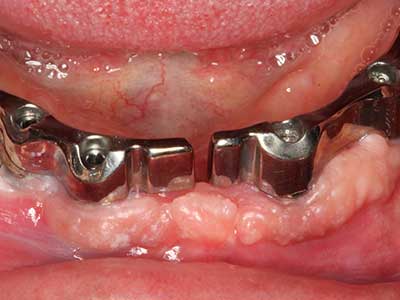

La piezochirurgia presenta altri vantaggi per quanto riguarda la raccolta di blocchi ossei. Oltre all'elevata precisione dell'osteotomia appena descritta, l'utilizzo di puntine per sega molto sottili permette di minimizzare in maniera significativa la perdita di materiale. È molto probabile che si verifichi una maggiore perdita di materiale durante la raccolta utilizzando puntine di strumenti più spessi, in particolare delle frese Lindemann (Lakshmiganthan, Gokulanathan et al. 2012). La separazione basale, necessaria in particolare per i trapianti di blocchi nella zona retromolare, viene semplificata grazie a seghe specificatamente progettate di forma rettangolare; di conseguenza la piezochirurgia è considerata una procedura precisa, semplice e sicura per la raccolta di blocchi di osso nella zona retromolare (Happe 2007) (figg. 1-12).

Il tessuto osseo non è semplicemente una struttura minerale, ma contiene anche una percentuale significativa di fibre di collagene. Ciò significa che non possiede solo una buona forza di compressione, ma anche un certo livello di flessibilità che è possibile sfruttare durante l'esecuzione degli accrescimenti di osso. Nella procedura di espansione classica con incisione ossea, la cresta alveolare atrofizzata viene incisa longitudinalmente ed espansa con cautela dopo aver raggiunto una profondità di osteotomia adeguata (figg. 13-16), idealmente senza una sostanziale rimozione del periostio (Brugnami, Caiazzo et al. 2014, Stricker, Fleiner et al. 2014). I sistemi a piastra e vite con distanza di espansione incrementale si sono dimostrati efficaci nella separazione delle due lamelle ossee restando al di sotto della soglia di frattura. In generale, sono richieste larghezze dell'osso residuo di almeno 3-4 mm (Chiapasco, Zaniboni et al. 2006) per garantire un'adeguata flessibilità e una copertura sufficiente dell'osso per gli impianti futuri. Se necessario, un'osteotomia di rilascio verticale su uno o più lati può migliorare la flessibilità. Una combinazione con ulteriori tecniche di accrescimento, in particolare dal lato buccale, è stata descritta come un'alternativa alla tecnica classica.

La procedura di incisione è particolarmente atraumatica e non comporta una perdita significativa di dimensione durante l'utilizzo delle seghe piezoelettriche, così come non si notano differenze rilevanti tra impianti in mandibole incise e impianti in una cresta alveolare senza deficit osseo (Chiapasco, Zaniboni et al. 2006, Danza, Guidi et al. 2009). Una sufficiente irrigazione continua è essenziale, tuttavia, in particolare con incisione profonda e localmente ristretta, per prevenire la sollecitazione termica nelle regioni apicali dell'osteotomia.